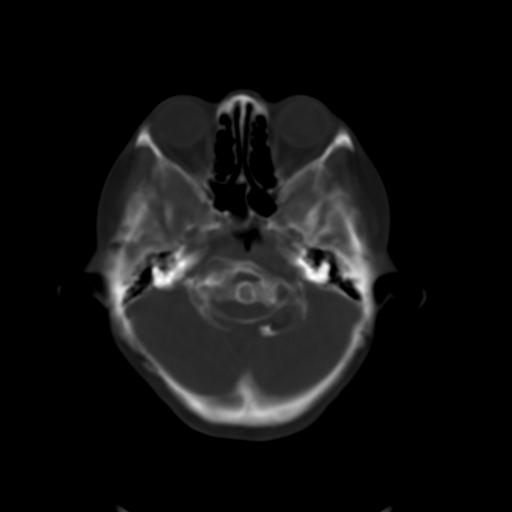

标题: CL0976:颅骨凹陷征 [打印本页]

标题: CL0976:颅骨凹陷征

女,56岁,头痛,没有其他的神经系统的阳性体征

颅底陷入是枕大孔周围骨,包括枕骨基底部、髁部和鳞部上升向颅腔内陷入的畸形。环、枢椎也随之上升、突入。多属枕骨及环枢椎先天性发育异常,也可继发于引起颅底软化的疾病、成骨不全或佝偻病等。

颅底凹陷症!这样横断位未见过,平时都是颈椎侧片所示。建议颈椎mr检查。

颅底凹陷是压迫小脑所以应该有受压的症状,如走路不稳,醉酒状态等.

颅底凹陷.典型.